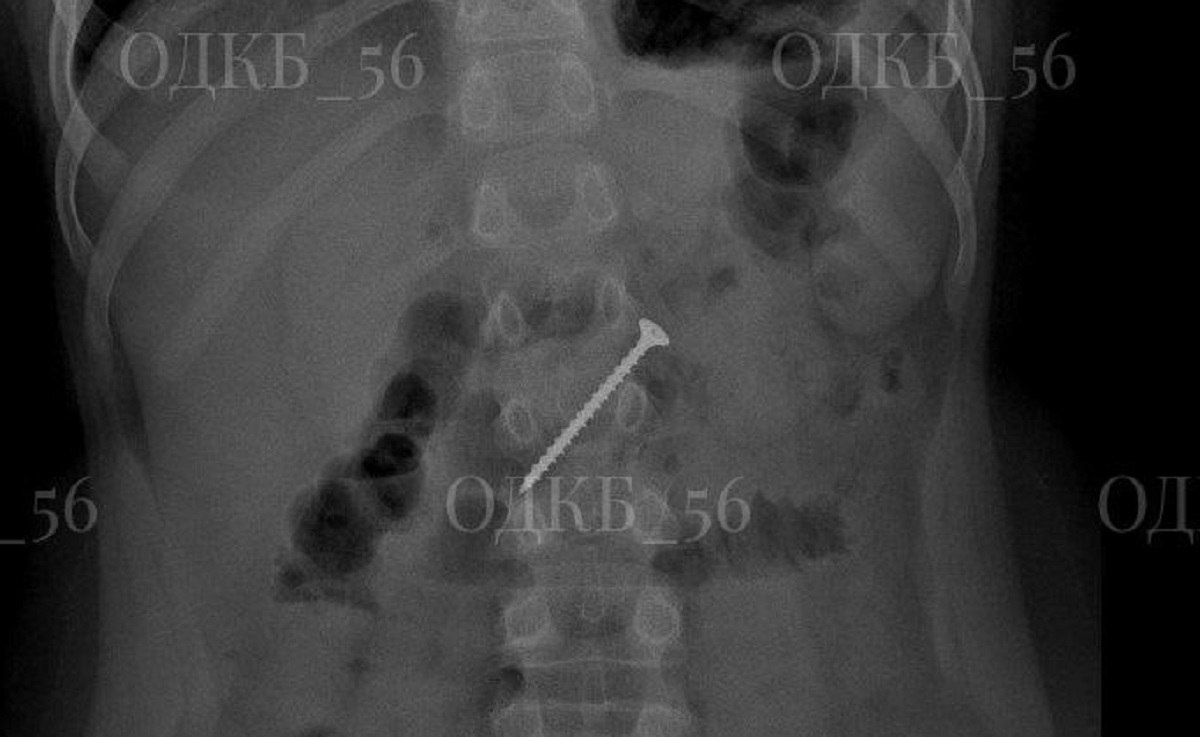

В ОРЕНБУРГЕ ВРАЧИ СПАСЛИ РЕБЁНКА, ПРОГЛОТИВШЕГО 5-САНТИМЕТРОВЫЙ САМОРЕЗ

В областной детской клинической больнице врачи провели экстренную операцию девятилетнему ребёнку, случайно проглотившему металлический саморез.